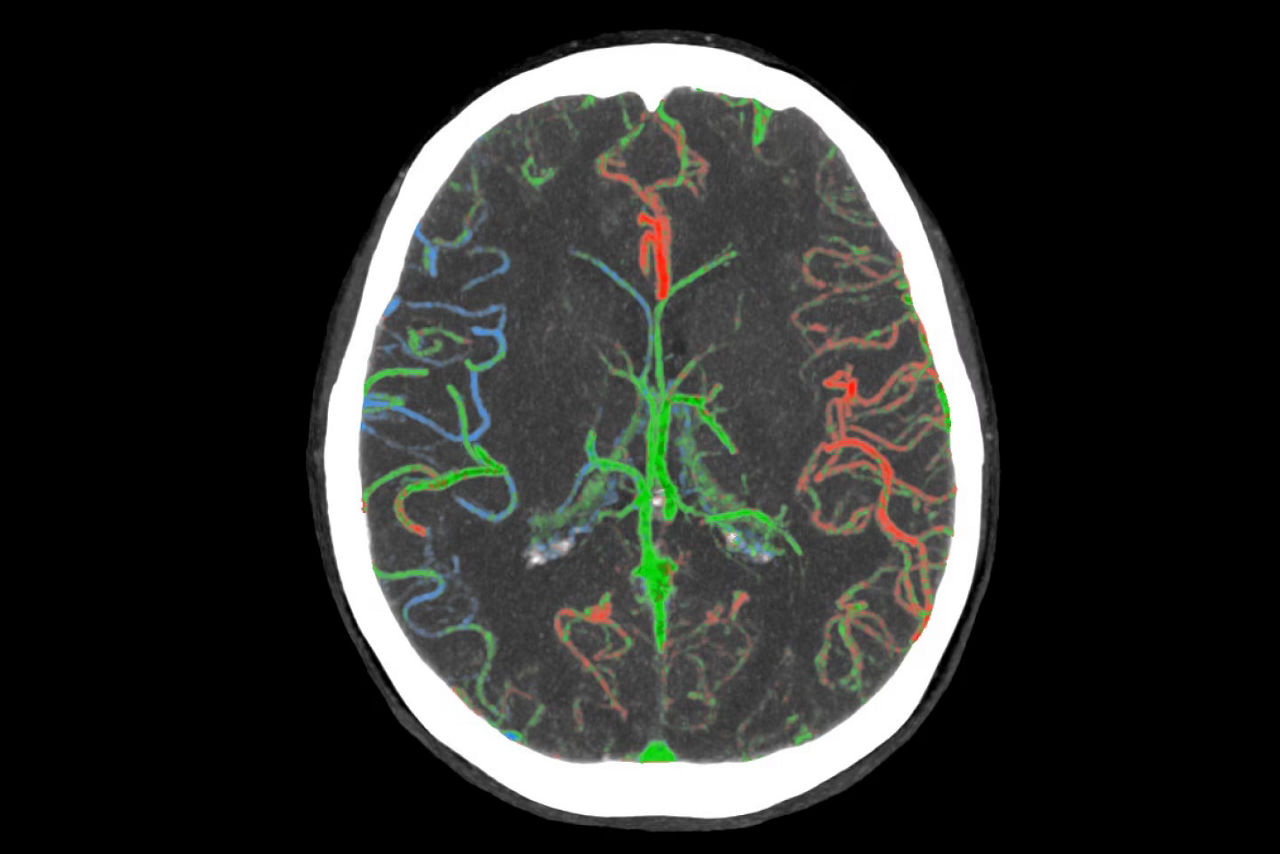

• ColorViz, an intelligent color-coded display enabling easy and confident identification of vascular enhancement timing

faststroke-interactive-workflow-ci-en